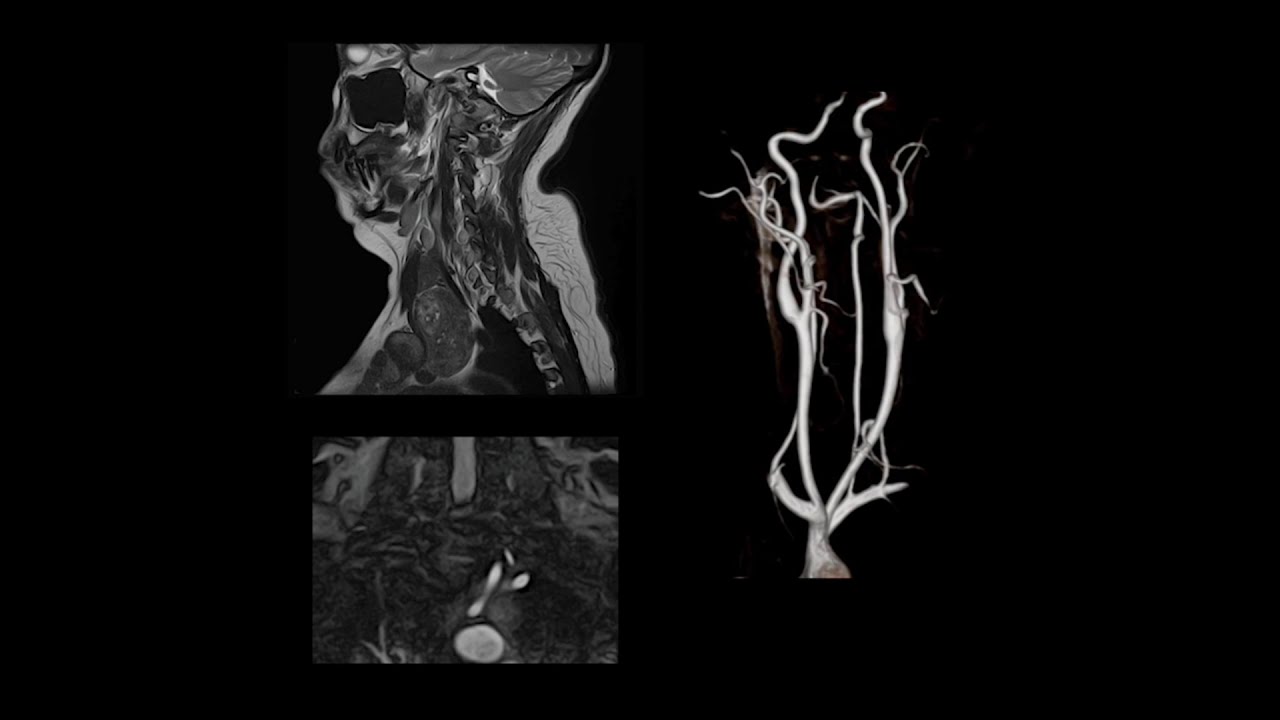

Time-Spatial Labeling Inversion Pulse (Time-SLIP) MRA

none CE MR Angiography

Time-SLIP is an Arterial Spin Labeling (ASL) variant that is typically used to depict blood vessels within a targeted region in any imaging orientation.

Canon MRI

Time-SLIP has been evaluated for use in the renal arteries, carotid arteries, pulmonary system and portal-venous system.It produces accurate angiograms using blood as an endogenous tracer, instead of a contrast agent.

It is very useful in patients with renal insufficiency